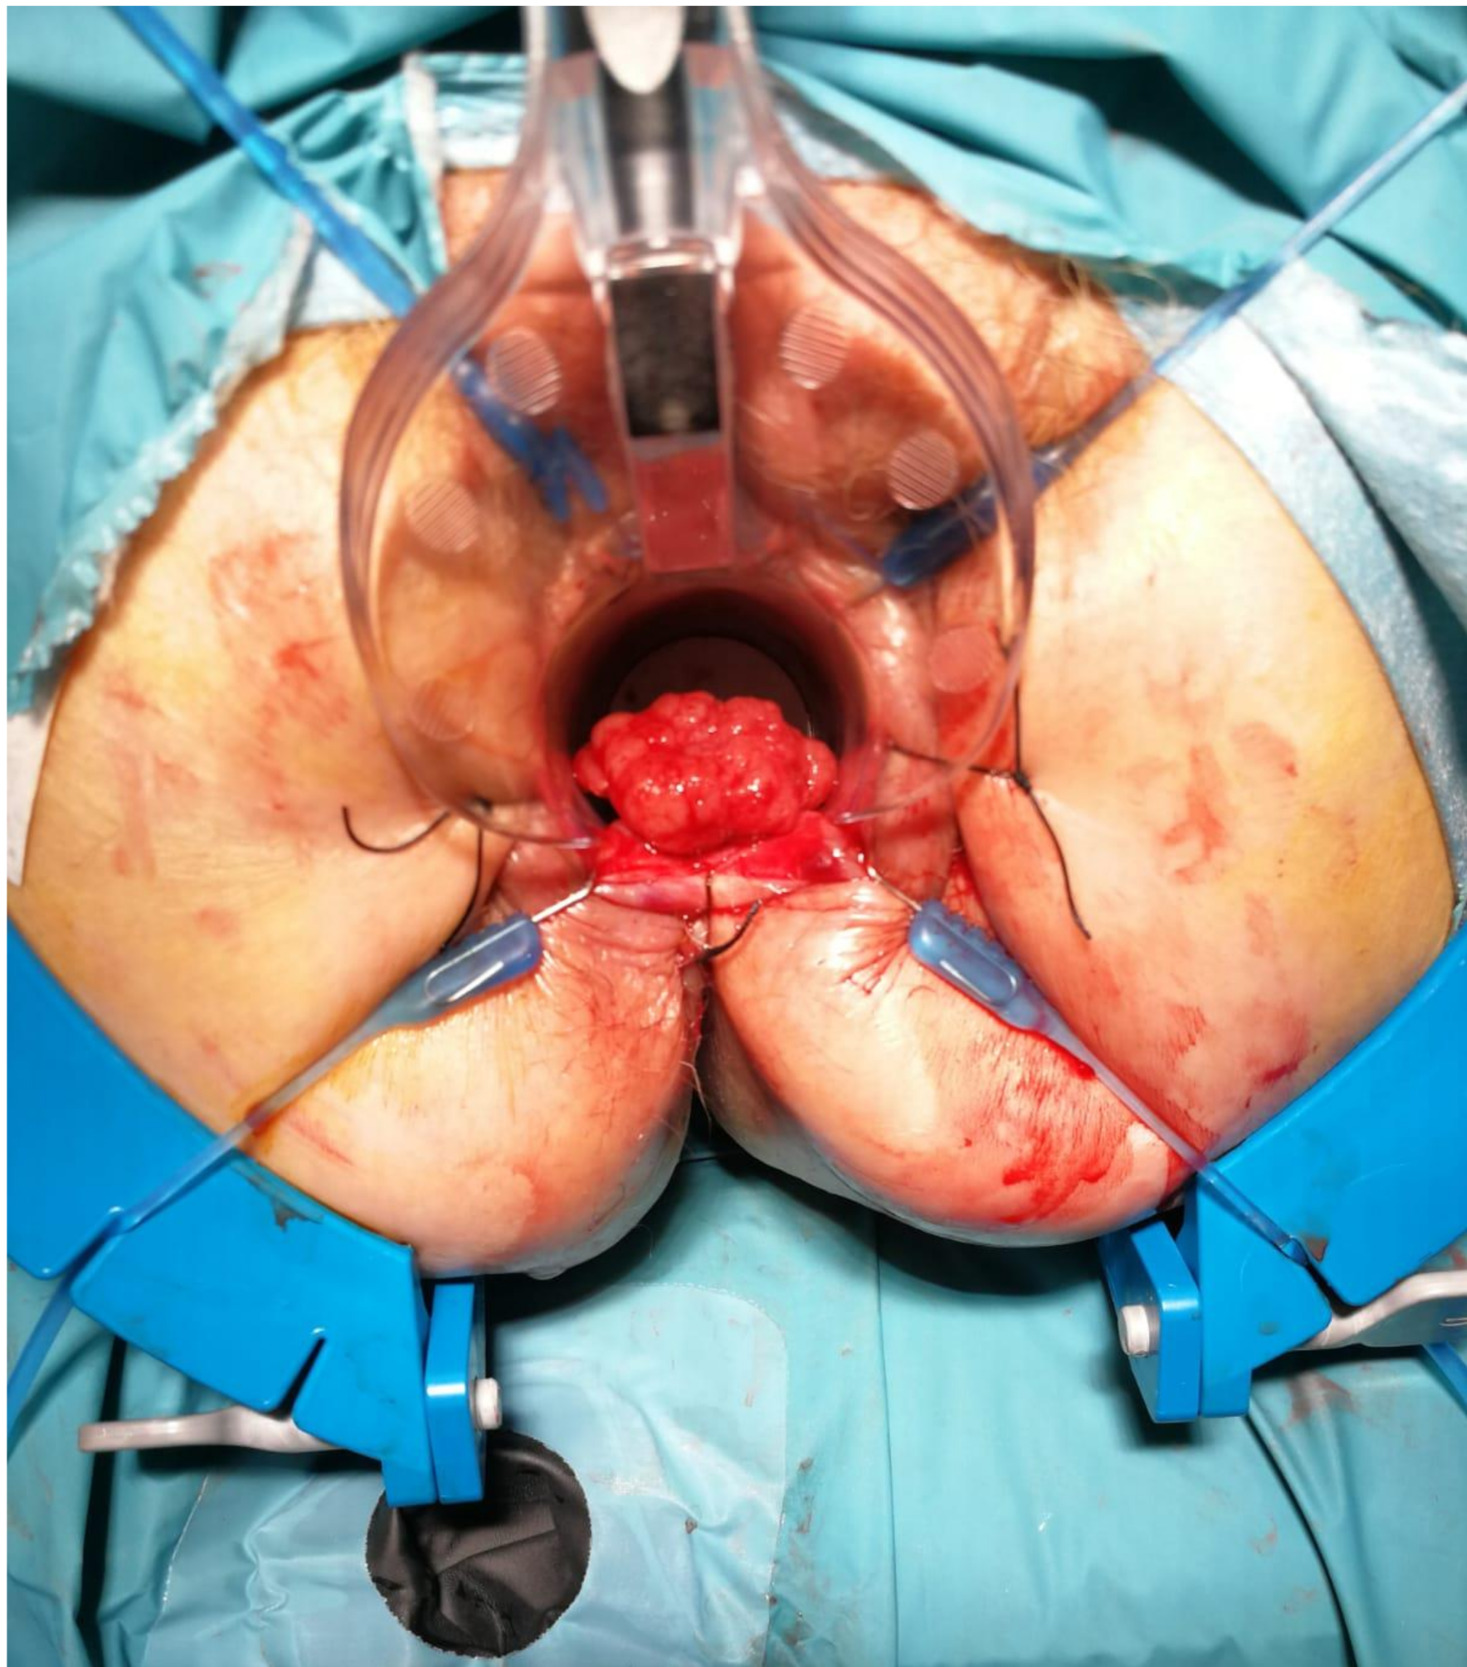

We report the case of a 52-year-old male patient in whom a vegetative lesion of the distal rectum was incidentally identified during urological evaluation for bladder carcinoma. The patient’s medical history was notable for episodes of hematochezia, which had not previously undergone proctological assessment. Endoscopic investigations were conducted (Figure 1); however, biopsy specimens yielded non-diagnostic results. Computed tomography (CT) imaging demonstrated apparent obliteration of the distal rectal lumen by a parietal mass measuring approximately 4 cm. To further characterize the lesion, contrast-enhanced MRI was performed, confirming the presence of an expansive mass in the distal rectum (Figure 2).

Inhomogeneous signal hyperintensity in T2-weighted sequences with a fluid/fluid level appearance, isointensity signal in T1-weighted sequences, no signal reduction in T1-weighted sequences in opposition of phase in agreement with the absence of a lipid component, no signs of signal restriction in diffusion (ADC 1.6), thin peripheral contrast enhancement, and thin septa in the structure were all features of the MRI. The lesion on the right posterolateral side appeared to affect the muscular coat, extending to the serosa raising suspicion for a teratomatous-type lesion. Following multidisciplinary consultation, surgical excision was planned. A transanal local excision was performed under general anesthesia (Figure 3). The patient’s postoperative course was uneventful, and he was discharged on the first postoperative day. Histopathological analysis revealed an edematous, ulcerated, and chronically inflamed segment of the large intestinal wall, containing lymphatic and intraparietal blood vessel ectasias consistent with hemolymphangioma. No postoperative complications were observed. The patient underwent regular follow-up evaluations, including proctological examinations, CT scans, and MRI studies (Figure 4) every six months for the initial two years, followed by annual assessments. At four years postoperatively, there is no evidence of disease recurrence.